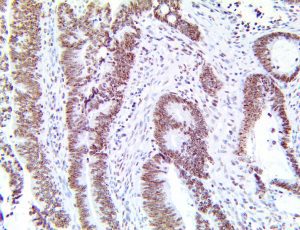

The first cytokines released are interleukin 1β (IL-1β) and tumor necrosis factor-α (TNF-α), which attract a variety of circulating white blood cells (WBCs) to the infection site, including neutrophils, monocytes, macrophages, and natural killer (NK) cells. This response, along with the antipathogenic chemicals released by these cells (i.e., complement), comprise the innate immune response. These cells directly attack the invading pathogen and also release additional cytokines, chief among them interleukin-1 and 6 (IL-6). IL-6 is essential for invoking the adaptive immune response, which calls T-cells, B-cells, and T helper (Th) cells to the infection site. IL-6 also stimulates further recruitment, proliferation and activation of macrophages.

This activation induces inflammatory monocytes to highly express IL-6, starting a localized and then systemic cascade effect that results in hyperproduction of IL-6, which accelerates the inflammatory process. Because IL-6 also increases vascular permeability, excessive levels cause blood vessels to become very leaky. This, along with clotting factors released from vascular endothelial cells, stimulates the coagulation cascade, resulting in microthrombosis (tiny clots), which leads to ischemia and tissue death of the kidney, intestines, heart, liver, brain and extremities.